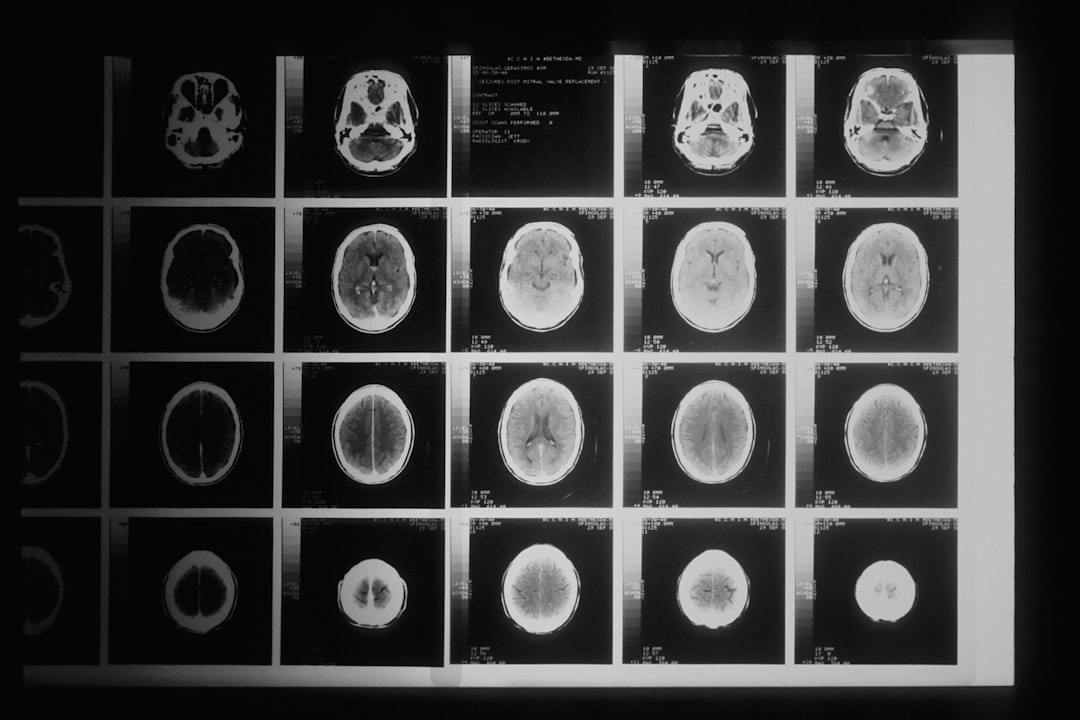

뇌 신경마비 증상 이해하기

뇌 신경마비 증상은 다양한 형태로 나타날 수 있으며, 이는 환자의 일상생활에 상당한 영향을 미칠 수 있습니다. 대표적으로 한쪽 팔이나 다리에 힘이 없거나, 근육의 조절이 어렵다는 증상이 있습니다. 이러한 증상은 신경에 대한 손상이 원인이 되어 발생합니다. 특히 뇌졸중이나 외상에 의해 발생하는 경우가 많아 신속한 대응이 필요합니다. 사람들은 이러한 증상을 겪을 때, 무척이나 불안하고 두려운 감정을 느끼게 됩니다. 그래서 이러한 증상들에 대해 이해하는 것이 중요합니다.

뇌 신경마비 증상은 여러 원인이 있을 수 있습니다. 가장 흔한 원인 중 하나는 뇌졸중이며, 이는 뇌로 가는 혈류가 차단되거나 뇌혈관이 터져서 발생합니다. 이로 인해 뇌의 특정 부분이 손상되어 신경 기능이 저하되며, 이 과정에서 뇌 신경마비 증상이 나타납니다. 따라서 뇌졸중 예방이 매우 중요하다고 할 수 있습니다.

같은 맥락에서, 종양이나 감염도 뇌 신경마비 증상의 원인이 될 수 있습니다. 뇌 안에 생기는 비정상적인 존재는 주변 뇌세포에 압력을 가할 수 있으며, 이로 인해 신경 기능에 마비를 일으킬 수 있습니다. 이러한 원인들을 정확히 이해하고 예방하는 방법에 대해 고민하는 것이 중요하겠습니다.